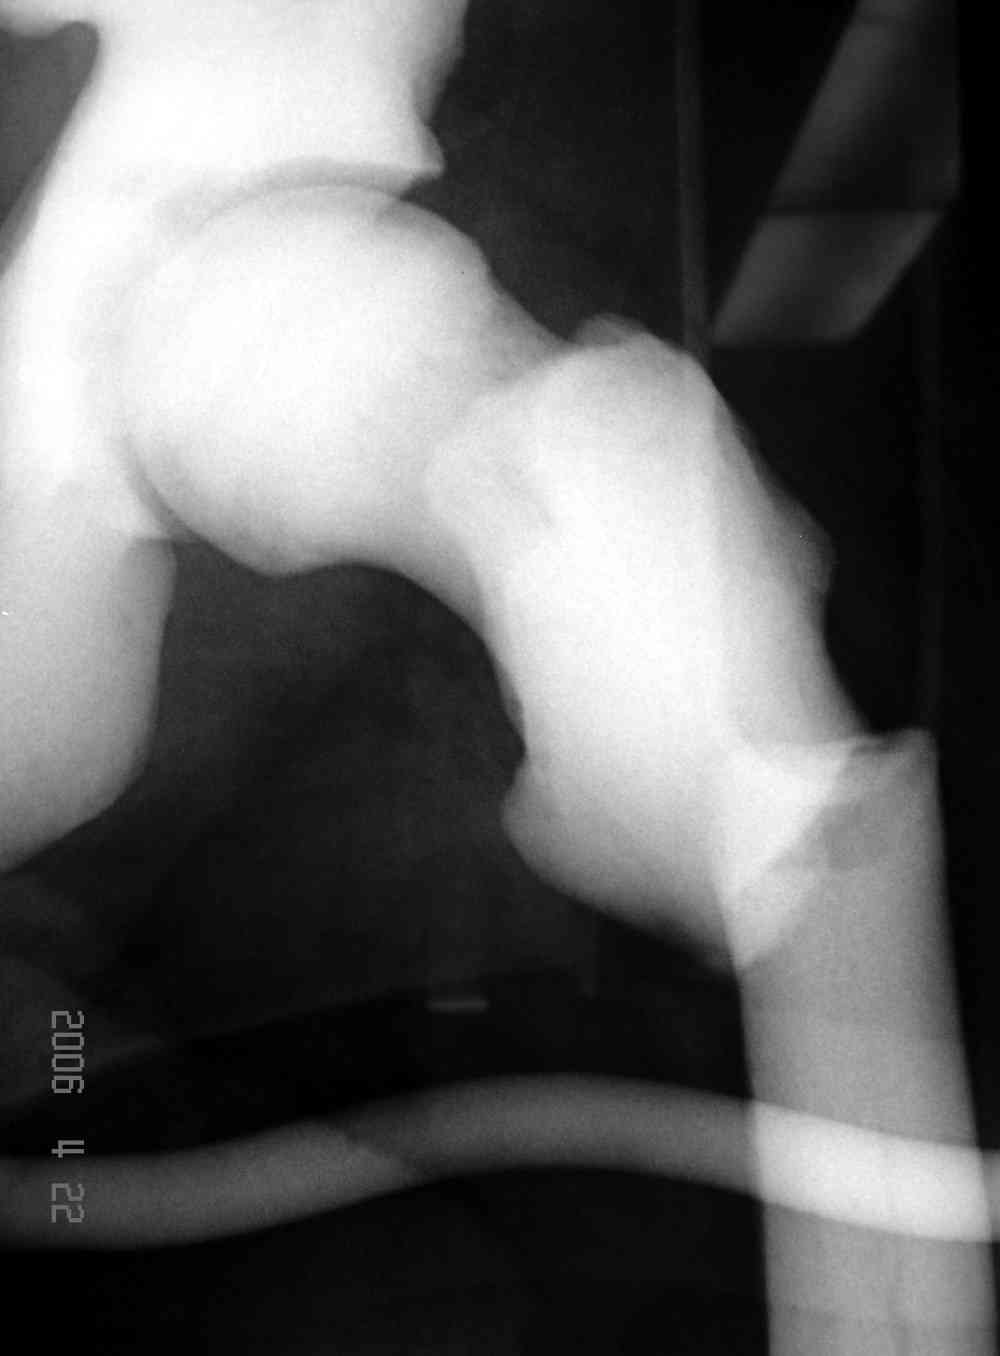

Уважаемый Константин Иванович! Полностью согласен с проф. Михайловым, данный случай не похож на мраморную болезнь, при которой имеется резкое, строго симметричное и генерализованное уплотнение костной ткани (остеопетроз), и кость оказывается построенной преимущественно из гомогенного компактного костного вещества. Для примера привожу случай из архива нашего института (бедренные, плечевые кости и таз, рис 1,2,3)

Изменения структуры костей у Вашего пациента больше похожи на полиоссальную форму фиброзной дисплазии или болезнь Педжета, возможены также инфаркты костного мозга б.берцовых костей. К сожалению, качество снимка не очень хорошее, непонятно, сохранен ли кортикальный слой б.берцовых костей по передней поверхности.